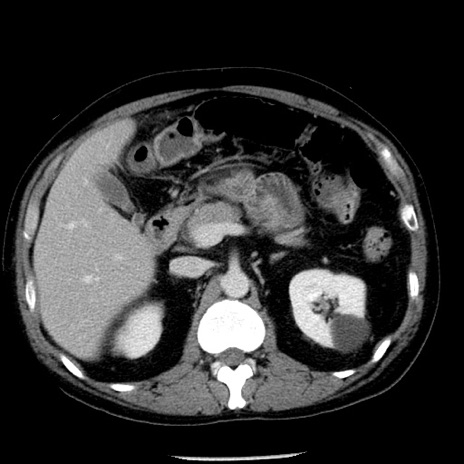

症例29(横断像)

【症例】40歳代男性

【現病歴】2日前から胃痛あり。徐々に周期的な激痛に変化した。本日になっても激痛があるため受診。

【身体所見】意識清明、BT 38-39℃台あり、腹部:膨満、やや硬、右下腹部に圧痛あり。

【データ】WBC 8500、CRP 23.26